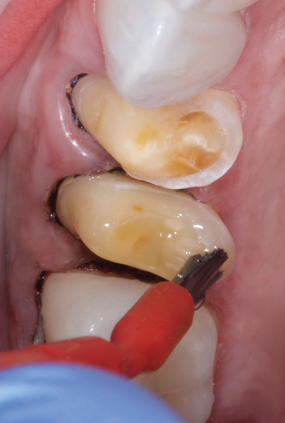

The next step in the APC protocol involves applying a zirconia primer that contains specialized adhesive phosphate monomers, including 10-MDP, to the surfaces of the zirconia that will be bonded (Figure 2).29,30 The monomer 10-MDP, which is also used in some dentin bonding agents and cements, has been shown to be particularly effective in bonding metal-oxide ceramics such as zirconia. Although zirconia primers may also increase the abilities of other cements, such as resin-modified glass ionomers, to bond to zirconia,31 it is highly recommended that clinicians only use such primers with the bonding agents and other products within their product lines and not try to mix and match products from different manufacturers. These products may have similar names, but they likely have different chemical compositions that may not be compatible with each other. Some clinicians may be confused by the fact that some zirconia and ceramic primers with specialized adhesive phosphate monomers also contain silanes, which make them universally applicable to various materials, including silica-based ceramics. But remember, silanes contribute no effect to the long-term strength of bonds to metal-oxide—based ceramics unless they are coated with a silica-based ceramic or silica-containing particles.12

(2.) Step P: immediately following air abrasion, a specialized ceramic primer with adhesive phosphate monomers is applied.

Figure 2

(3.) Prior to placing the restorations, the enamel of the abutment teeth is selectively etched with phosphoric acid for 20 seconds and a self-etch dentin primer is applied.

Figure 3

(4.) Prior to placing the restorations, the enamel of the abutment teeth is selectively etched with phosphoric acid for 20 seconds and a self-etch dentin primer is applied.

Figure 4

(5.) Step C: the restorations are inserted with a dual-cure composite resin, and the excess composite material is cleaned with a sable brush.

Figure 5